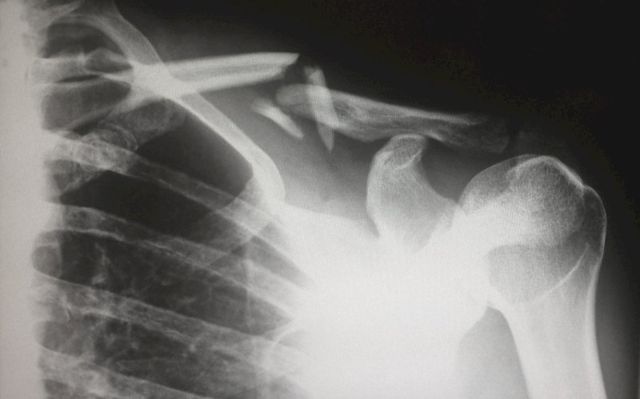

Пластическая хирургия — это не только красота, это еще и устранение дефектов и деформаций, восстановление функций органов, нарушенных в результате травм. Возьмем, как самый понятный пример, типичное, весьма частое во время боевых действий пулевое (или осколочное) глубокое ранение конечности.

Вот пуля прошла в руку или ногу, втащила в рану фрагменты одежды и амуниции, разорвала мышцы, перебила кость – и застряла. Бойца перевязали на поле боя – прежде всего остановили кровотечение и купировали болевой шок. И повезли туда, где есть хирург. Не пластический, просто военный, просто хирург. Тот почистил рану, убрав и клочья одежды, и землю, и обрывки мягких тканей раненого. Сшил мышцы, какие смог сшить. Как смог, «сложил» перелом в более-менее нормальное положение, запустил антибиотикотерапию, дабы избежать нагноения. И далее раненый стал выздоравливать. А вот теперь один нюанс.

Возвращаемся к раненому. Идет время, он выздоравливает, кость срослась, мышцы срослись и даже могут работать – а конечность в целом не работает, потому что ее рубцы не пускают. Держат прочнее канатов.